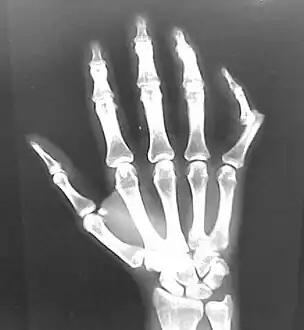

X-rays are usually taken to confirm a diagnosis and detect any fractures which may also have occurred at the time of dislocation. A dislocation is easily seen on an X-ray.[16]

- Finger: Interphalangeal (IP) or metacarpophalangeal (MCP) joint dislocations[31]